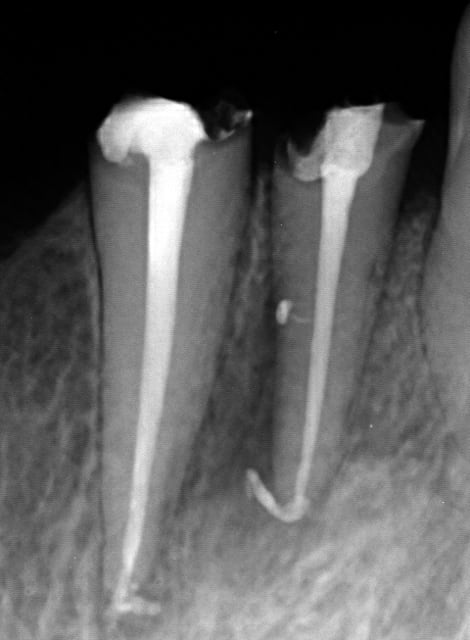

Endo 4  1  lime cass e preop ewbdub - Eugenol

Endo 4  2  lime cass e lime pass e apsetj - Eugenol

Endo 4  3  lime cass e racine obtur e xfgnty - Eugenol

Endo 4  4  ime cass e fin nbax19 - Eugenol

Pour sortir les limes cassées j'ai un insert satelec endo, mais là elle était trop loin et dans la courbure (j'ai oublié la pré-op je la met demain).